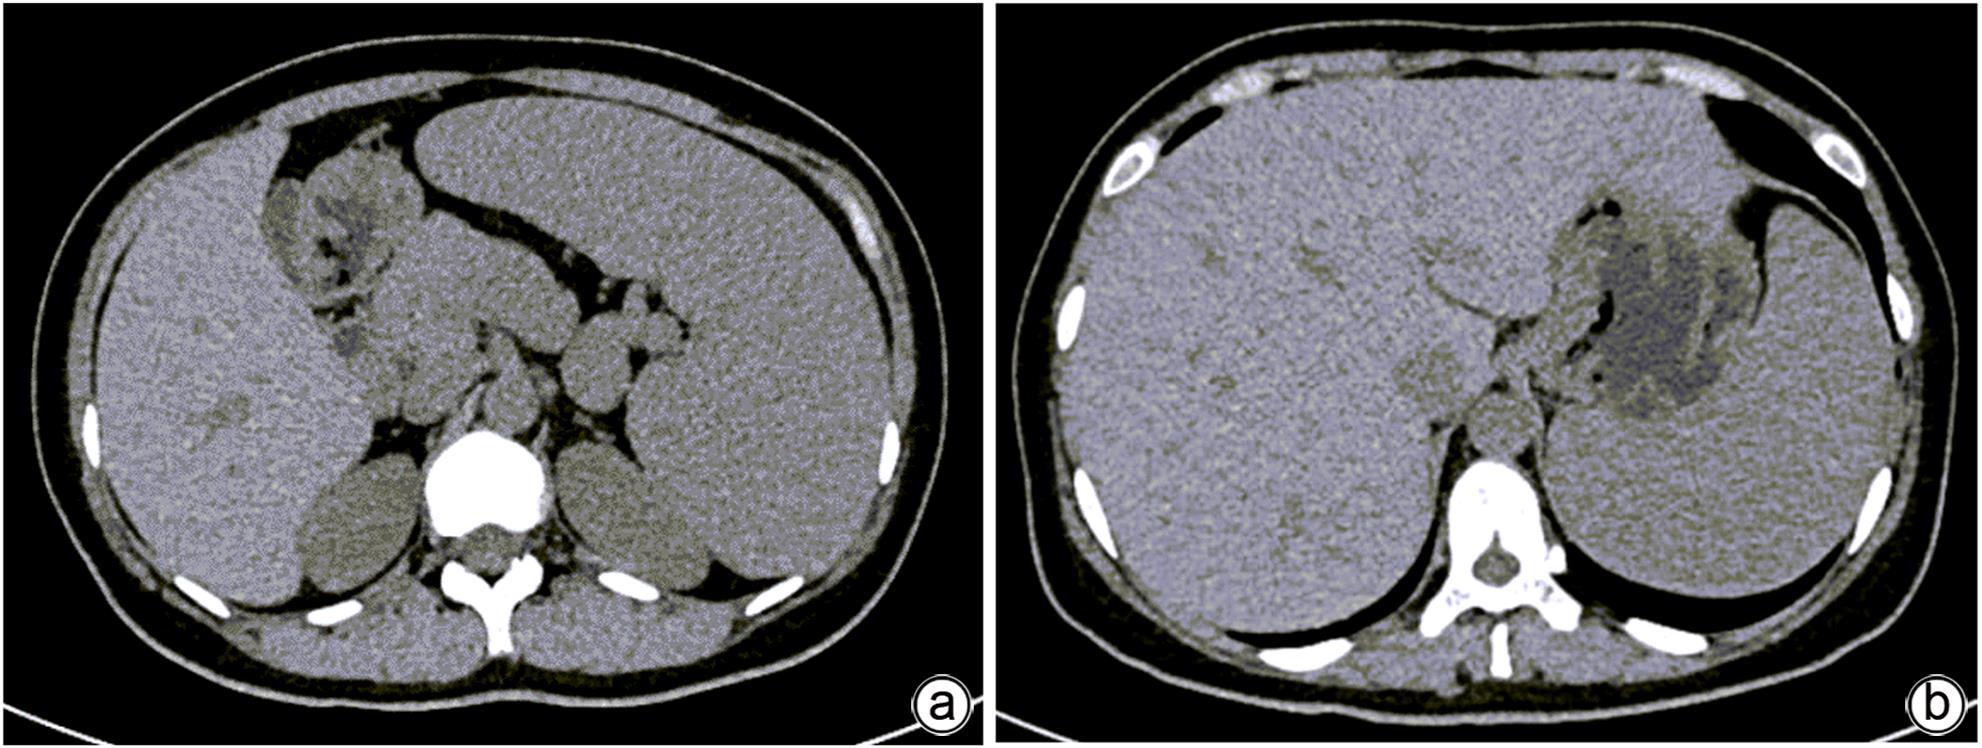

摘要: 本文报道以“肝脾肿大待查”为主诉,经各项检查确诊为B型尼曼-皮克病的案例,并通过文献复习,总结B型尼曼-皮克病肝脏受累的异质性表现,旨在提高疑难罕见肝脏疾病的临床诊治水平。

Abstract: This article reports a case with the chief complaint of “hepatosplenomegaly to be investigated” and a confirmed diagnosis of Niemann-Pick disease type B after various tests, and a literature review was conducted to summarize the heterogeneous manifestations of liver involvement in type B Niemann-Pick disease, in order to improve the clinical management of difficult and rare liver diseases.-